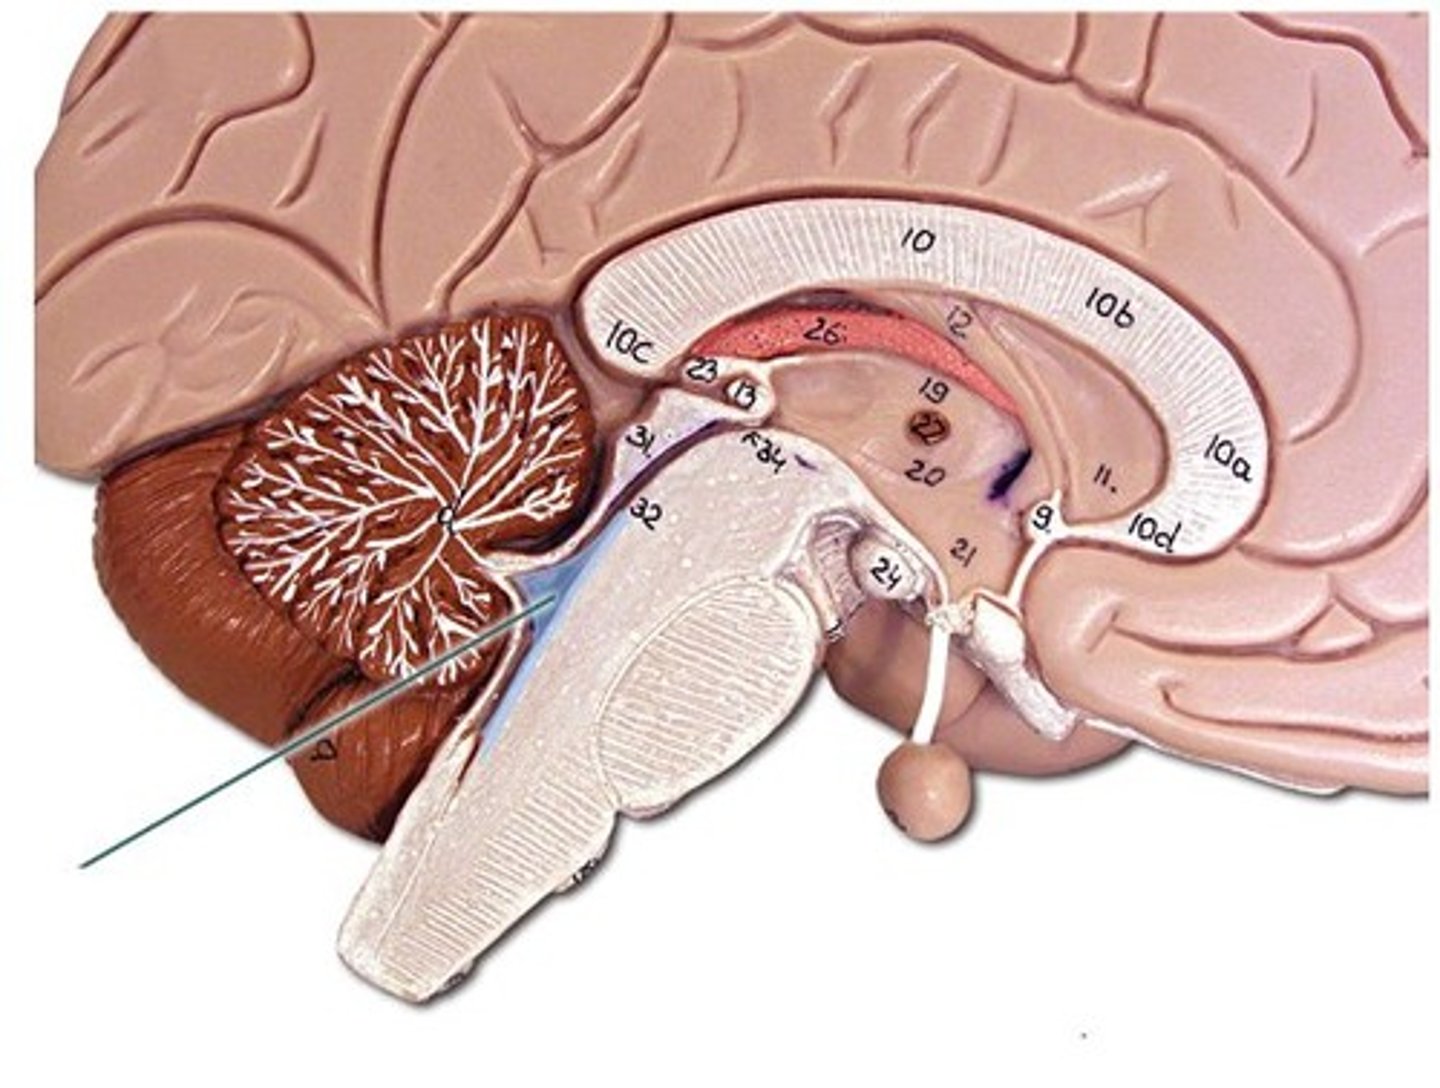

Corpus callosum

Fornix

Septum pellucidum

Pineal Gland

Arbor Vitae

Cerebellum

pons

Pituitary Gland

Fourth Ventricle

Intermediate mass of the thalamus

spectum pellucidum

Thalamus

Hypothalamus

Cerebral Aqueduct

Medulla Oblongata